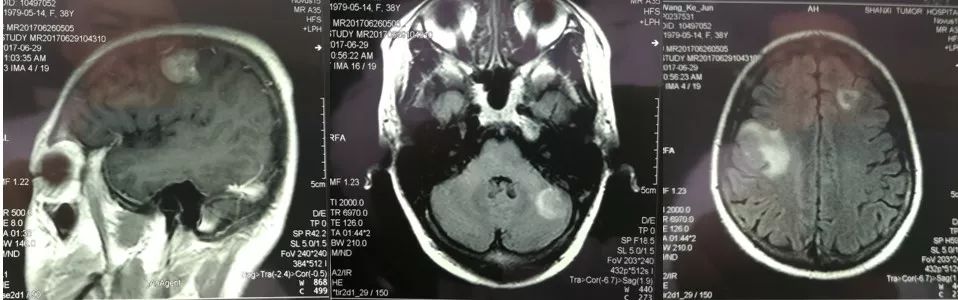

2017年5月复查头颅MRI时提示脑转移(图3),于6月起行脑转移瘤局部6MV-X线外照射调强放疗(共计95%PGTV 60.0 Gy/25次/33天, 95%PTV 40.0 Gy/25次/26天, 95%PGTV 50.0 Gy/25次/33天),转移灶病变有所缓解。于2017年9月起行二线内分泌联合抗HER2治疗,具体治疗方案为:戈舍瑞林+氟维司群同时联合曲妥珠单抗至今,未见明显其他复发和转移征象(图4)。

图3 头颅MRI提示脑转移(2017年5月)

图4 头颅MRI(2018年7月)